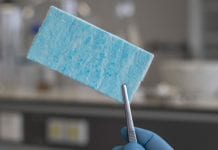

Setting the new standard for managing surgical bleeding and organ leakage

GATT Technologies has developed a game-changing solution targeted to set the new standard in managing bleeding and organ leakage.

Managing surgical bleeding and preventing organ...